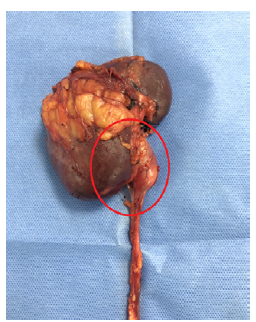

Transurethral cystoscopy revealed no endoluminal bladder lesions, however during surgery, a tumor of approximately 5cm in diameter was discovered in the right renal pelvis with no macroscopic involvement of adjacent tissues; no retroperitoneal adenopathies were observed on macroscopic examination (Figures 3 and 4). It should be noted that nephroureterectomy with bladder cuff was performed using the intravesical approach.

Source: Photographs obtained during the study.

Figure 4 Approach to the area of interest (in red). Projection of the mass contained in the right renal pelvis.